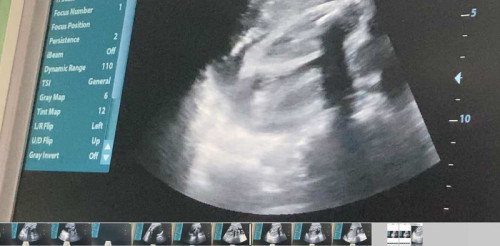

ช่วยดูเพศให้หน่อยค่ะแม่ๆ

หมอบอกน้อง หนีบไม่ยอมอ้าขา แต่ดูแล้วน้องไม่มีไข่ค่ะแม่ หมอบอกอาจลุ้นอีกทีคลอดเลย ตอนนี้ 7 เดือนกว่าเตรียมของไม่ถูกเลยค่ะแม่ๆ

เหมือนจะเป็นผู้หญิงนะคะแม่

ขอบคุณนะคะแม่ บ้านนี้อยากได้ลูกสาวมากๆค่ะ💕